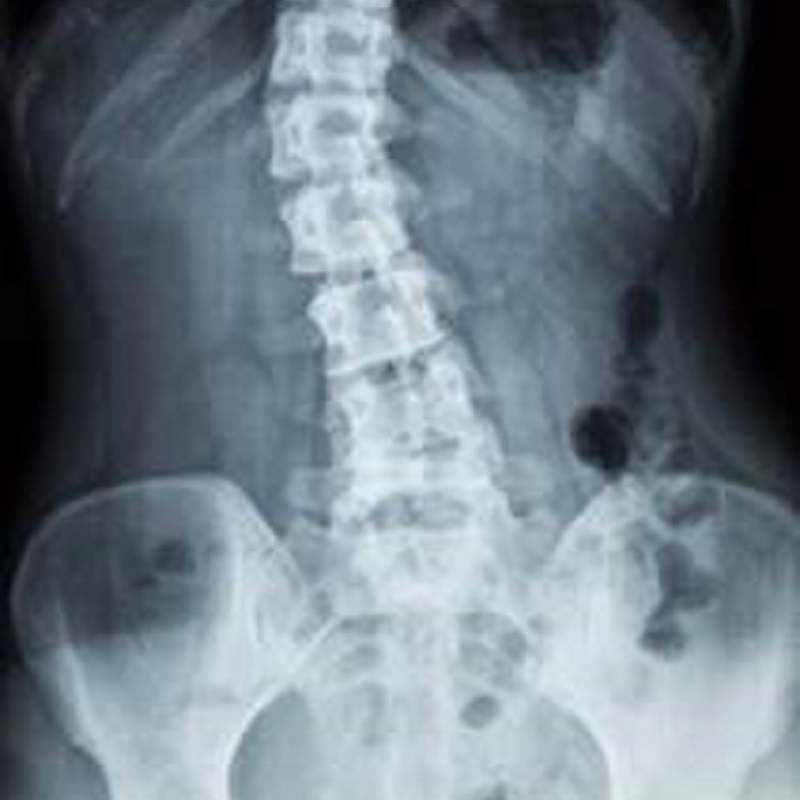

- 脊柱側彎

脊柱側彎:

冠狀面或額狀面脊柱非直線型狀,呈C字型或S字型。可再分為功能性和結構性脊柱側彎。